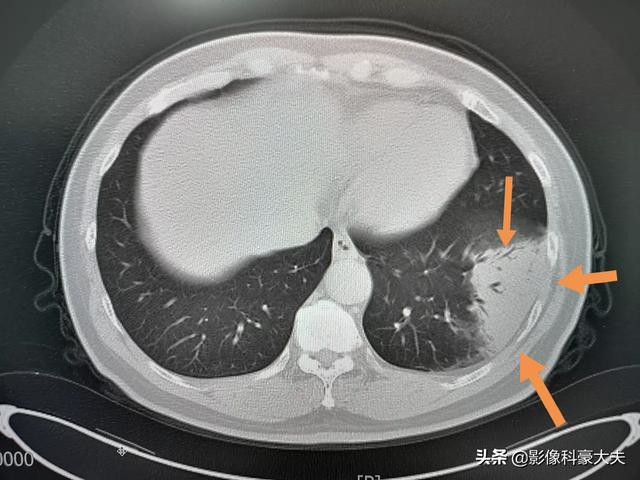

この中年男性は、3日間の咳と発熱があり、CTで左下肺炎が認められ、亜分節に沿って分布し、比較的高密度であった(地硝子影ではない)。肺門側に気管支気腹徴候が認められ、血球数の増加を伴っていたため、コロナウイルスではなく、一般的な肺炎であった。

抗生物質で治療し、9日後にはかなり吸収され、現在は退院している:

②胸部CTを撮影すると、初期には多発性の斑状陰影や間質性変化を示唆することがあり、肺外帯に明らかで、その後の検討で両肺に多発性の地中影や浸潤影が生じ、重症例では固形肺病変が出現する。

②.肺炎の画像的特徴が胸部に認められる。

初期には複数の小さな斑状影と間質性変化を呈し、両肺に多発する地硝子影や浸潤影へと進行し、重症例では肺に固形変化が生じ、一般に「白い肺」と呼ばれる状態になることもある。